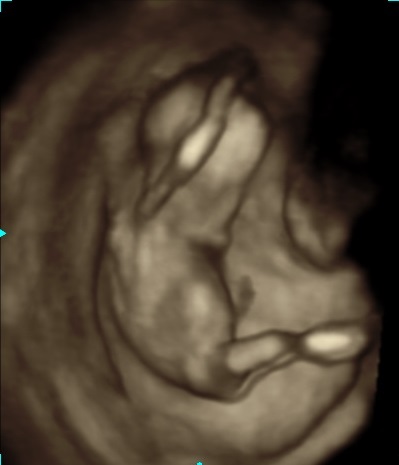

Attachment 19527Attachment 19528At my NT scan at 13 weeks (baby measured 14 weeks 1 day) the tech said if she had to bet she would say it is a girl. Yesterday I had a scan at 16 weeks(not sure where baby is measuring) with my ob he said he's not an expert but that he agrees with the tech that baby is a girl and that we can tell family just not announce on facebook(not a problem for me :) ). I'm still nervous that our little girl is actually a boy that's why I would love some more opinions/guesses from you all. Thanks!